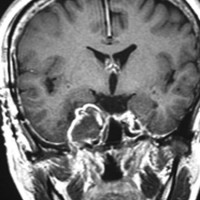

ちょっと大きめの三叉神経鞘腫

メッケル腔(ガッセル神経節)という場所から発生した三叉神経鞘腫のMRIです。サイズは放射線治療するには大きすぎます。ですから手術摘出します。手術には側頭開頭硬膜外法と経鼻内視鏡手術があります。内視鏡手術は三叉神経が外側に来ているので優位性があります。開頭手術では,側頭部の前の方を小さく開頭して脳の硬膜の外から腫瘍を見るだけで取れます。もちろん脳の損傷は起こさないようにしなければなりません。手術中には三叉神経が薄く広がって腫瘍のまわりにくっついていますからそれを大事に守りながら腫瘍を取っていきます。

手術のすぐ後のMRIです。幸いなことにこの患者さんでは,腫瘍を全部取ったのですが三叉神経の大部分を残すことができて,顔のしびれはとても軽くてすみました。全摘出すると経鼻手術でも開頭手術でも多少の顔面の痺れ(感覚低下)はでますが,日常生活に支障のないレベルに留めなければなりません。